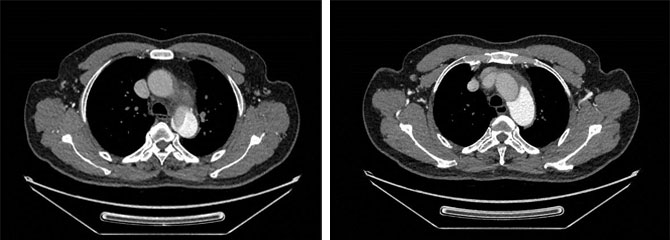

案例二:急性逆撕性A型主动脉夹层的微创治疗

第二例患者为58岁男性,他“突发胸腹痛”,到外院就诊被诊断为急性逆撕性A型主动脉夹层,随时可能发生主动脉破裂引致生命危险。传统治疗方案建议进行升主动脉置换和全主动脉弓置换手术,但由于该手术需要正中开胸、体外循环以及心脏停跳,患者无法接受,最终放弃了治疗。

患者转诊至我院后,李欣医生根据患者的具体病情,精心设计了微创治疗方案。李欣和杨珏医生通过仅5cm的胸骨上段小切口,在非体外循环下成功为患者实施了升主动脉至双侧颈动脉、左锁骨下动脉旁路移植术和胸主动脉夹层腔内隔绝术。术中主动脉造影确认主动脉夹层破口已完美封堵,术后患者恢复良好,第7天顺利出院。微创技术不仅成功挽救了患者生命,还避免了传统手术带来的巨大创伤。

术前CT